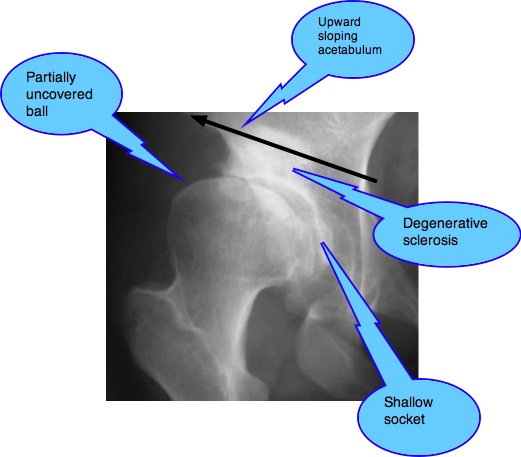

The young adult with a greatly increased range of motion of the hip, particularly if associated with pain in the groin, should be regarded with a high degree of suspicion. X-ray of the pelvis to assess the shape and size of the acetabulum is mandatory.

A 24-year old woman presented six months ago, complaining of chronic thoraco-lumbar pain. There was no mention of hip or groin pain.

Routine examination of the hip revealed greatly increased range of motion of the right hip and, on palpation extreme tenderness of the hip capsule and Pectineus and Adductor magnus muscles. The insertion of the Psoas major in the upper femur was red hot.

X-ray examination of the spine revealed no abnormalities but, in the radiograph of the right hip, the typical shallow acetabulum and partially unroofed head of femur typical of DDH were to be seen. She was not a breech birth, and had no history (I asked her mother to accompany her for the Report of Findings) of hip problems as an infant or in childhood. Certainly there was never mention of HIP DYSPLASIA ORTOLANI GALEAZZI.

My first thoughts before seeing the X-rays were of a Maignes Syndrome, referring pain to the groin. Ultimately I have decided that it's vice versa: The hip is referring pain to the back, mediated via the Psoas major and the Cluneal nerves.